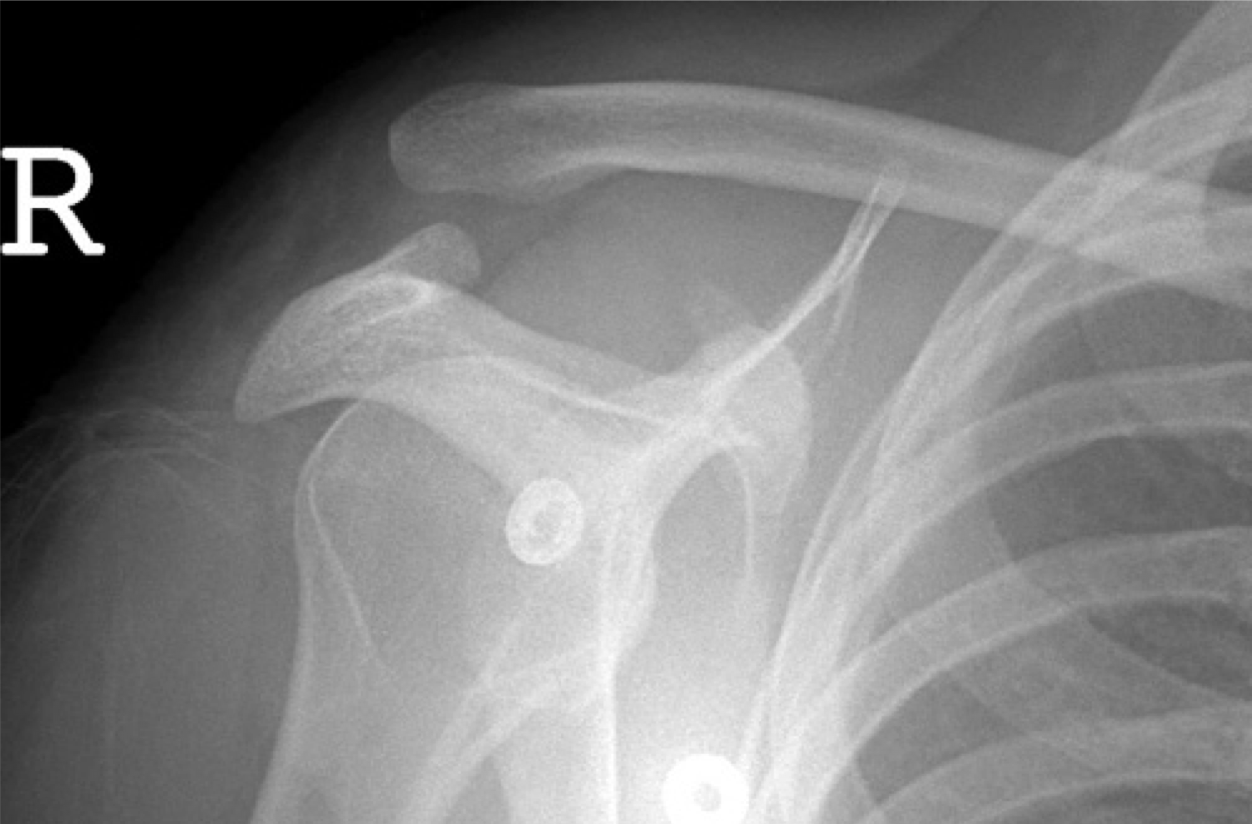

Clinical case: A 46 year old man was thrown from his bike. He had pain and deformity of his right shoulder.

What can you see? What is your diagnosis based on the patient’s presentation? Would you request an X-ray?

Does this x-ray confirm diagnosis of AC dislocation?

Yes - separation of acromion and clavicle